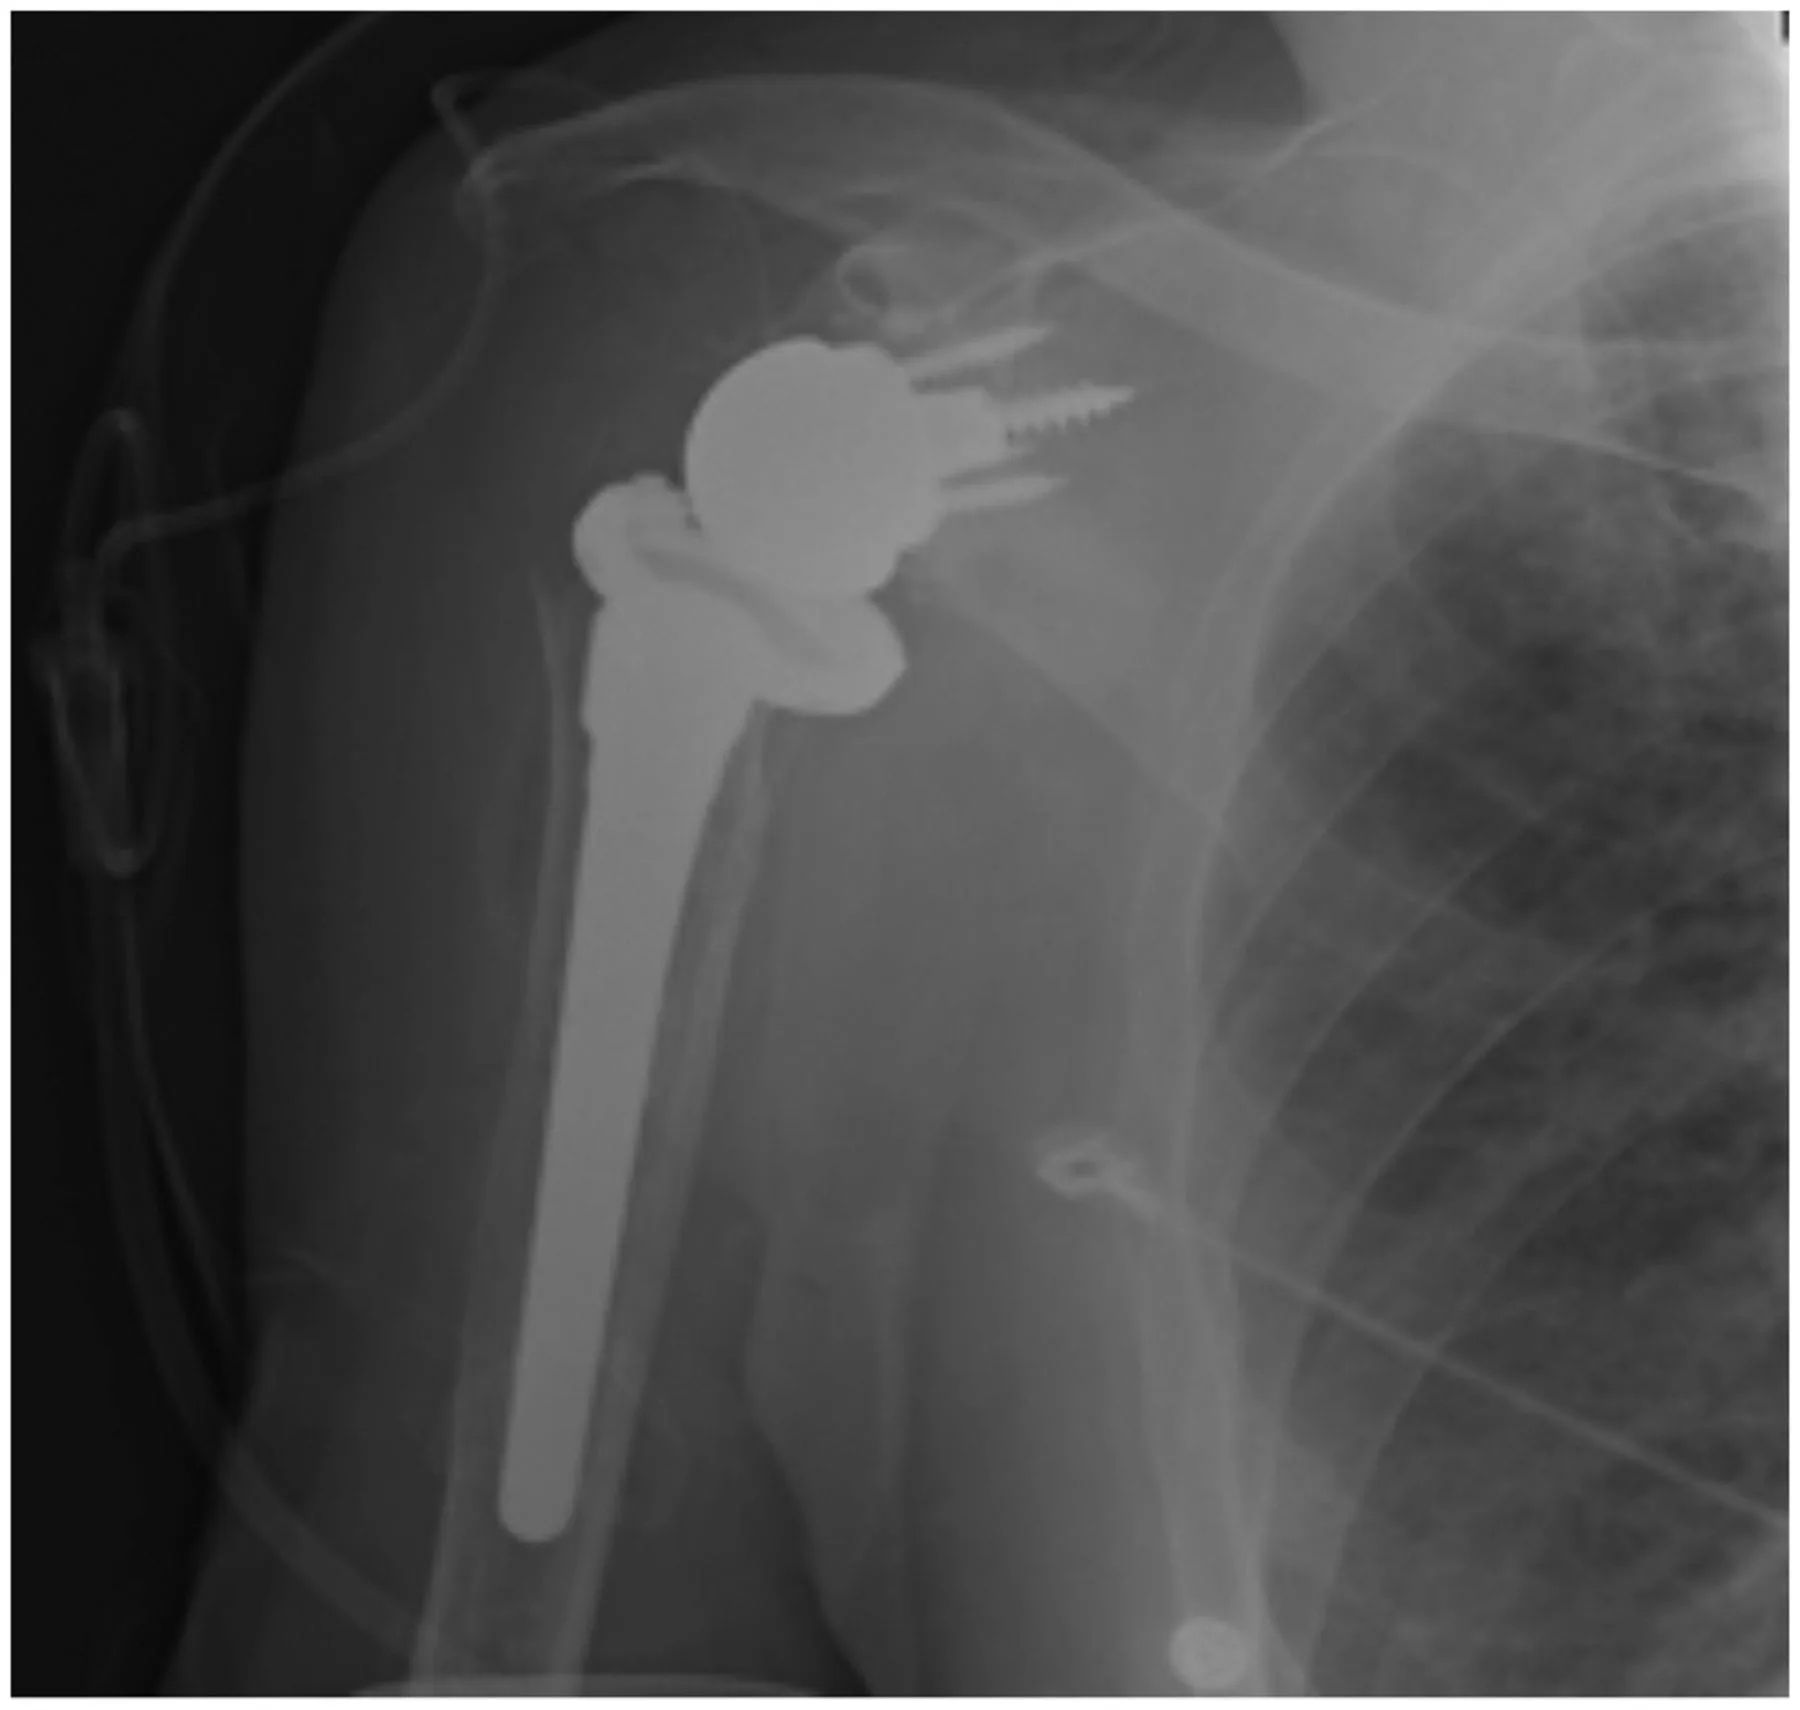

His main area of interest is the development of new methods and implants to prevent periprosthetic infection and bacterial biofilm formation on prosthetic devices, with particular focus on orthopaedic implants such as total joint prosthetics as well as biologic substrates such as bone allografts.